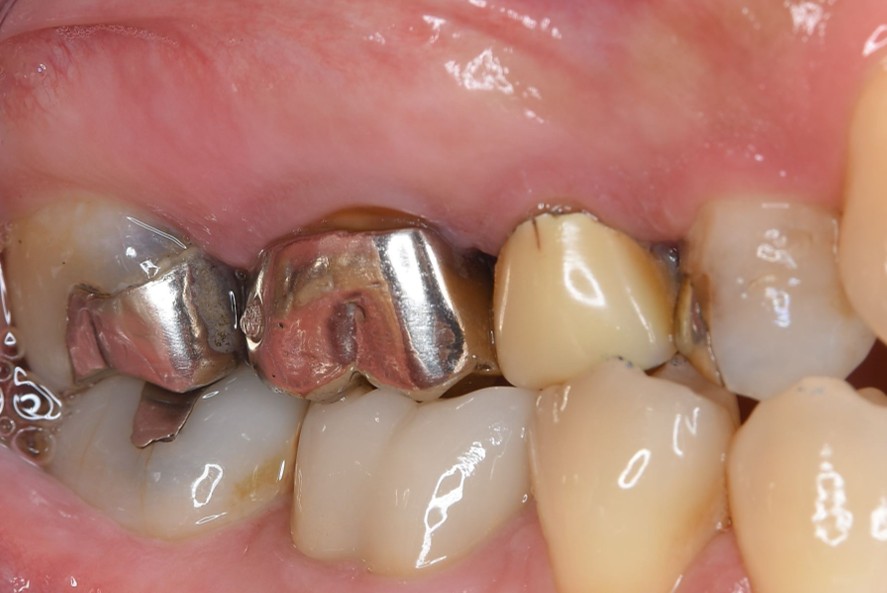

症例1:パーフォレーションリペア症例

(歯の中に大きな穴が空いてしまっているのを埋めて再生を促す治療)

歯に穴が空いていて骨に炎症がある状態 |

BEFORE |

AFTER |

人為的根穿孔を起こした部分に感染を起こしており、歯周ポケットが9㎜ありました。 ラバーダム防湿とマイクロスコープを使用して丁寧に治療を行いました。 殺菌性があり歯を補強することのできるMTAという根管充填材料を使用して、歯周ポケットは2㎜に改善しました。 |